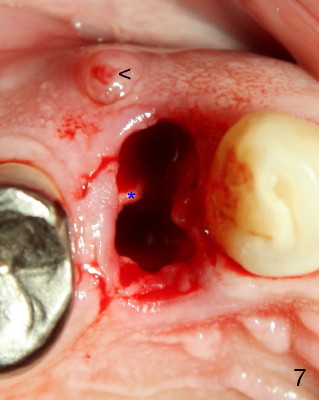

A 68-year-old male patient presented to office in March 2011 with chief complaint "upper right tooth is not comfortable". Clinical exam shows missing teeth: #13,14,30, and 31, replaced by removable partial dentures. The tooth #5 has mild mobility and percussion. Pocket depth is within normal limit. X-ray shows no significant finding (Fig.1,2). Three months later, he returned with chief complaint "The tooth has swelling". It appears that there is exostosis on buccal aspect of upper teeth. There is no erythema or tenderness on buccal mucosa around the tooth #5). But X-ray shows periradicular radiolucency (arrowheads in Fig.3,4). Cone Beam CT was recommended to confirm diagnosis of root fracture. Approximately one month later, abscess developed with fistula formation. Symptoms were controlled by taking Amoxicillin. On August 2, 2011, the patient returned for prophylaxis. The fistula was present (arrowhead in Fig.5). Gutta percha #30 was inserted into the fistula. PA was taken. The point of the gutta percha (blue arrowhead in Fig.6) points to enlarged periradicular radiolucency (black arrowheads). Deep pockets were in distobuccal and lingual. Decision was made to extract the tooth. Fig.7 shows the socket immediately extraction. The buccal plate is perforated. The septum (*) is not intact. Cracking sounds were heard during extraction. In fact the lingual root is obliquely fractured with exposed post (Fig.8: *). There is another cracking line from the buccal root to the lingual one (arrowhead). In brief, the earliest sign of root fracture is nonspecific. It should alert us to its suspicion.